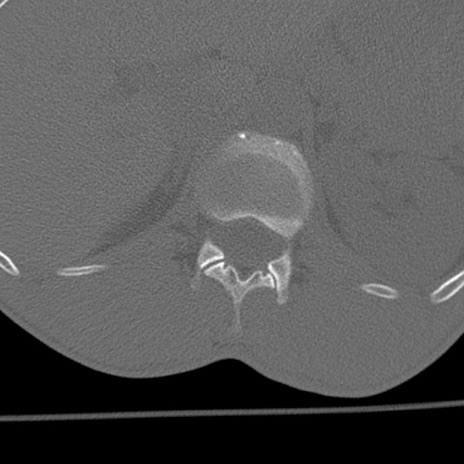

症例3 腰椎CT(横断像)

腰椎CT